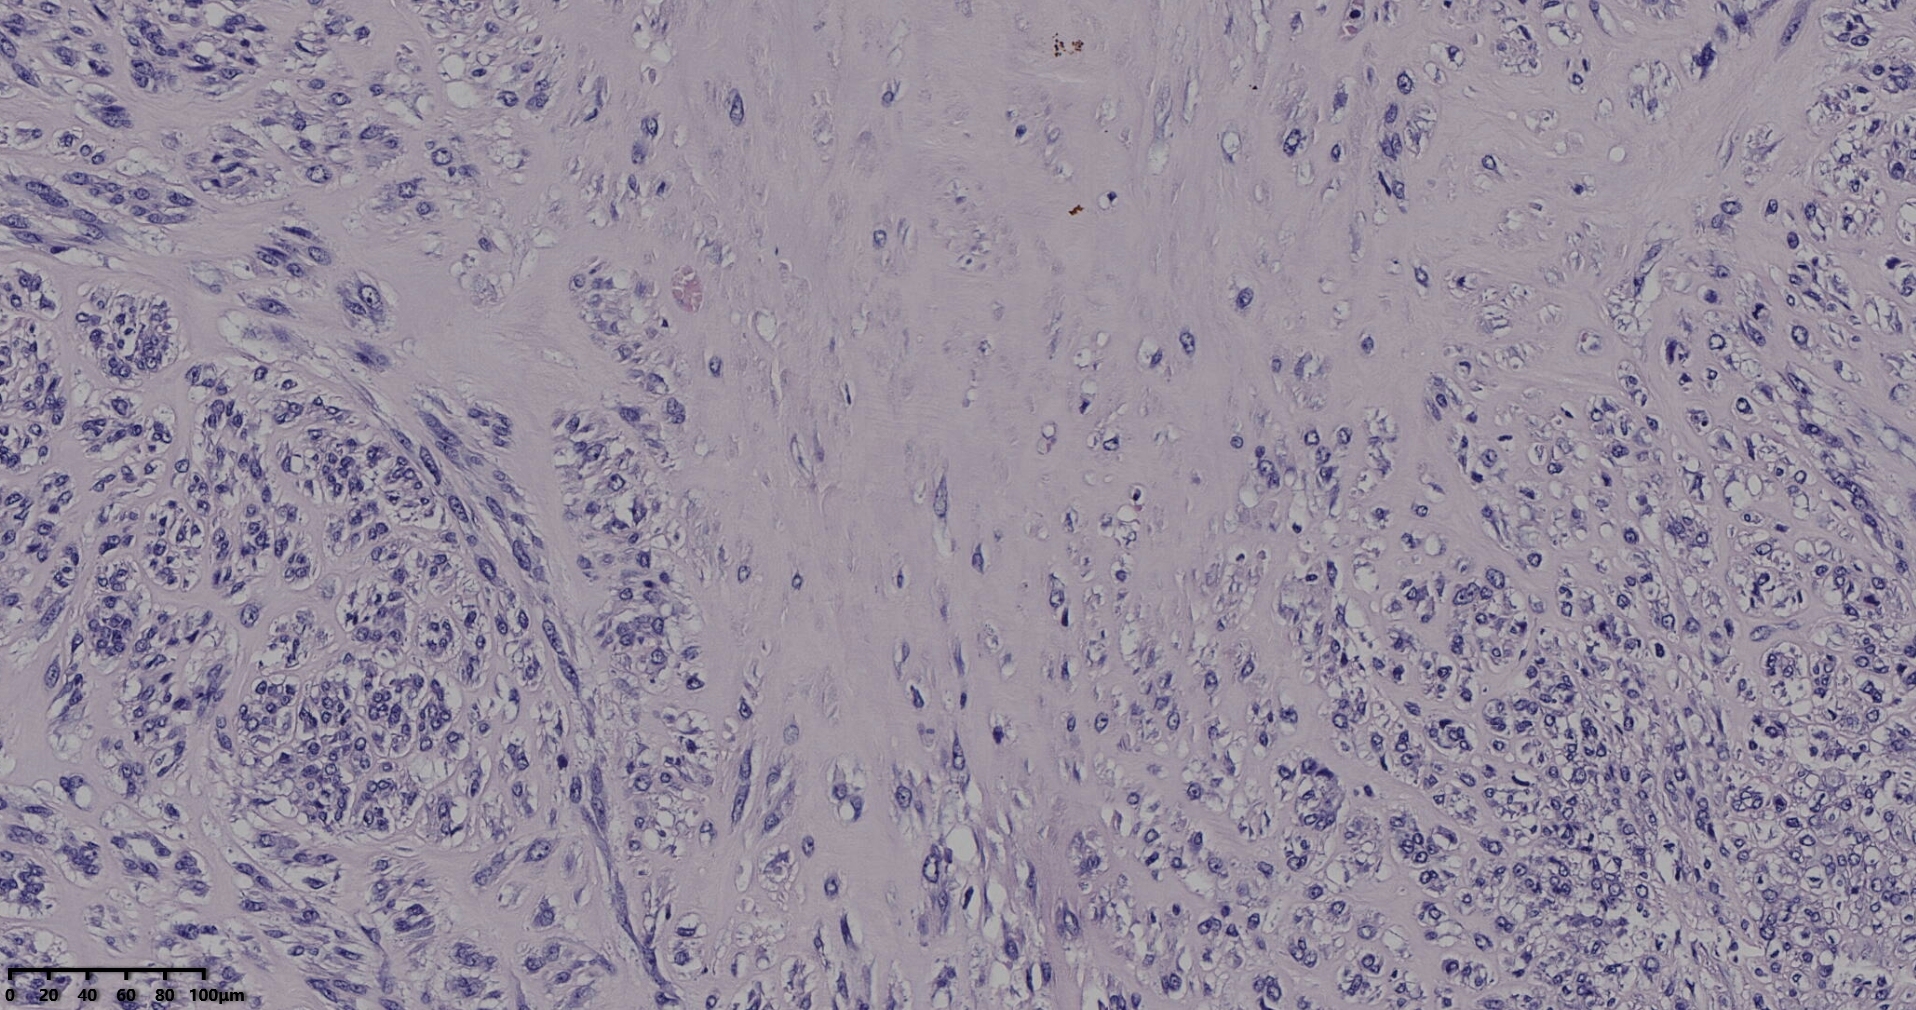

送检灰白肿物十余个,直径多在2-3厘米,切面均为灰白、实性,质地韧,其中一个大肿物,直径约7厘米,切片灰白灰红,质地韧当时取材时印象还是平滑肌瘤,伴变性,不考虑肉瘤,因为形态规整,质地韧,不脆,切面灰白,不是灰黄。

镜下所见小肿物无特殊,大肿物瘤细胞密集,中心区有变性、坏死,瘤细胞核有异型性。大肿物补充取材,发现,部分区域切面灰黄,这个区域,瘤细胞更密集,异型性更显著。肿物边缘有薄层正常平滑肌组织被覆,靠近边缘瘤细胞最密集,局部瘤组织内小血管较丰富。

会诊:考虑平滑肌肉瘤。

北医三院会诊:子宫平滑肌瘤伴红色变性可能性大,建议加做免疫组化及NGS检测进一步明确诊断。